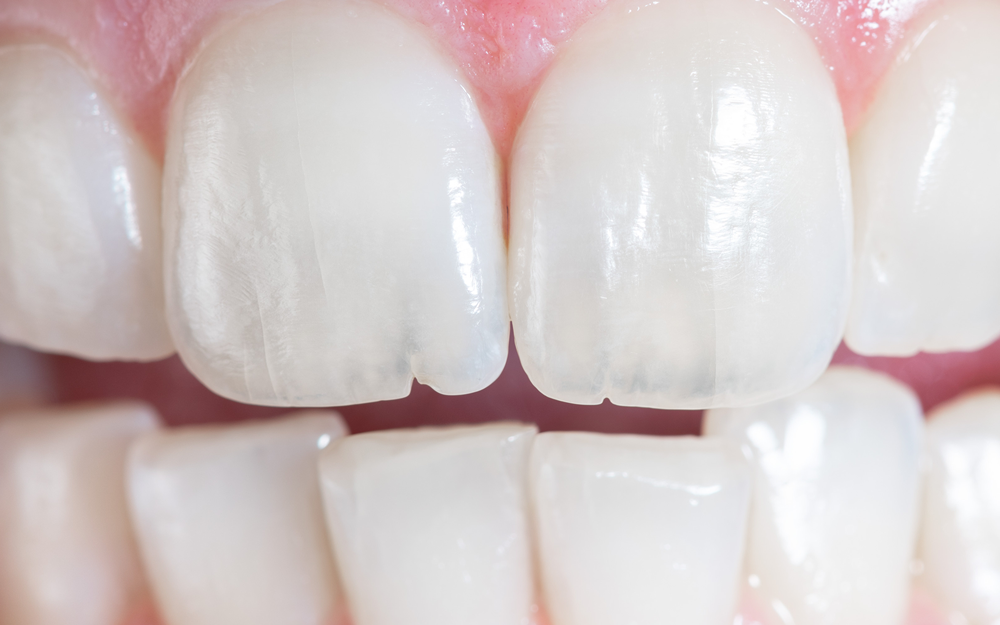

STEP 01. 치아 표면에 국한된 균열

증상 : 씹는 면에 실금처럼 보입니다.

통증이 거의 없습니다.

치료 : 강한 치아 저작과 이악물기 등 악습관 인지 후

습관 개선이 필요하며, 원내에서 교육 및

경과 관찰합니다.

증상 : 씹는 면에 실금처럼 보입니다. 통증이 거의 없습니다.

치료 : 강한 치아 저작과 이악물기 등의 악습관 인지 후

습관 개선이 필요하며, 원내에서 교육 및 경과 관찰합니다.